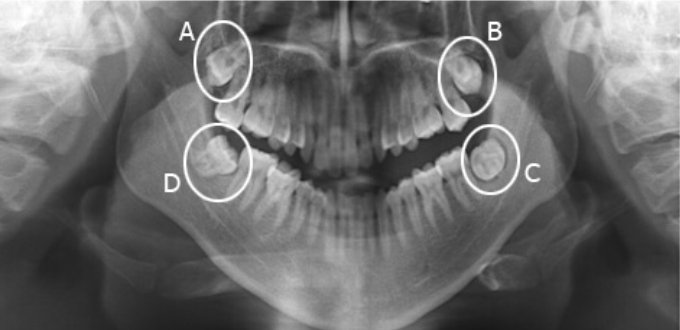

Đến với Nha khoa Dentel, mỗi khách hàng sẽ chụp X-quang cùng máy CT Cone Beam trong quá trình thăm khám tổng quát. Phim X-quang và phim 3D sẽ cho phép bác sĩ có thể thấy rõ được hình dáng, kiểu mọc của răng khôn. Từ đó đưa ra một phương án nhổ sao cho phù hợp mà lại an toàn.

Răng 8 là răng có các kiểu mọc phức tạp. Đặc biệt là phần chân răng. Để có thể chuẩn đoán chính xác cũng như lên phương án nhổ phù hợp, khách hàng sẽ tiền hành chụp phim X-quang, phim 3D với thiết bị công nghệ cao. Nhờ đó có thể thấy rõ hình dáng hoàn chỉnh chiếc răng 8, ngay cả trong trường hợp mọc ngầm bị lợi trùm, mang lại một phác đồ điều trị chuẩn xác – hoàn hảo.

Với phim chụp X-quang, phim chụp cắt lát từ máy CT Cone Beam, cho phép xác định rõ tới từng milimet. Giúp bác sĩ có thể tránh tuyệt đối những khoảng giới hạn không xâm phạm cũng như không gây tổn thương tới mô mềm và vùng răng bên cạnh. Nhờ đó mà bạn có thể yên tâm lựa chọn Nha khoa Dentel để thực hiện loại bỏ răng khôn nhanh chóng – an toàn và hiệu quả.

Phim chụp cắt lát trước khi nhổ răng khôn